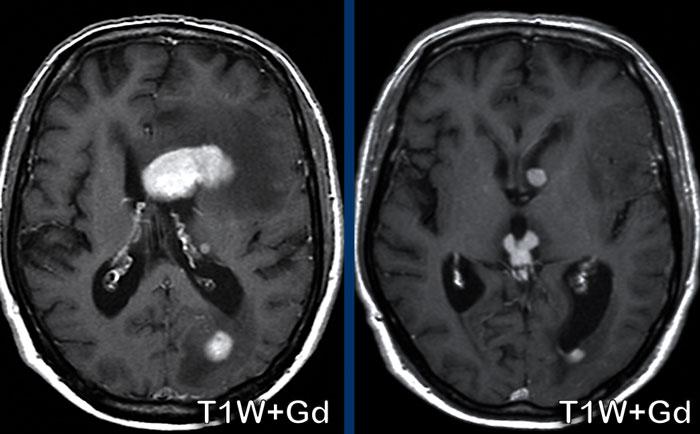

Các hình ảnh này của bệnh nhân ung thư phổi di căn. Ghi nhận hai tổn thương di căn ngấm thuốc tại bán cầu não trái.

Trên chuỗi xung T1W có tiêm thuốc tương phản từ Gadolinium, các mạch máu cũng ngấm thuốc mạnh khiến việc phát hiện các tổn thương di căn trở nên khó khăn.

Trên chuỗi xung “black blood” (xóa tín hiệu máu), tín hiệu của máu trong lòng mạch bị triệt tiêu, giúp nhận diện các tổn thương di căn ngấm thuốc dễ dàng hơn.

Ở bệnh nhân này, điểm nổi bật là một tổn thương dạng nang lớn ở thùy đỉnh phải với vòng viền ngấm thuốc không đều và một phần dày.

Có hiệu ứng khối và phù não xung quanh, không có hạn chế khuếch tán.

Có thể nghĩ đến u thần kinh đệm.

Tuy nhiên, còn có nhiều tổn thương khác ở các vị trí xa nhau.

Một trong số đó có vị trí đặc trưng tại ranh giới chất xám – chất trắng (mũi tên).

Các tổn thương này được xác định là di căn não.